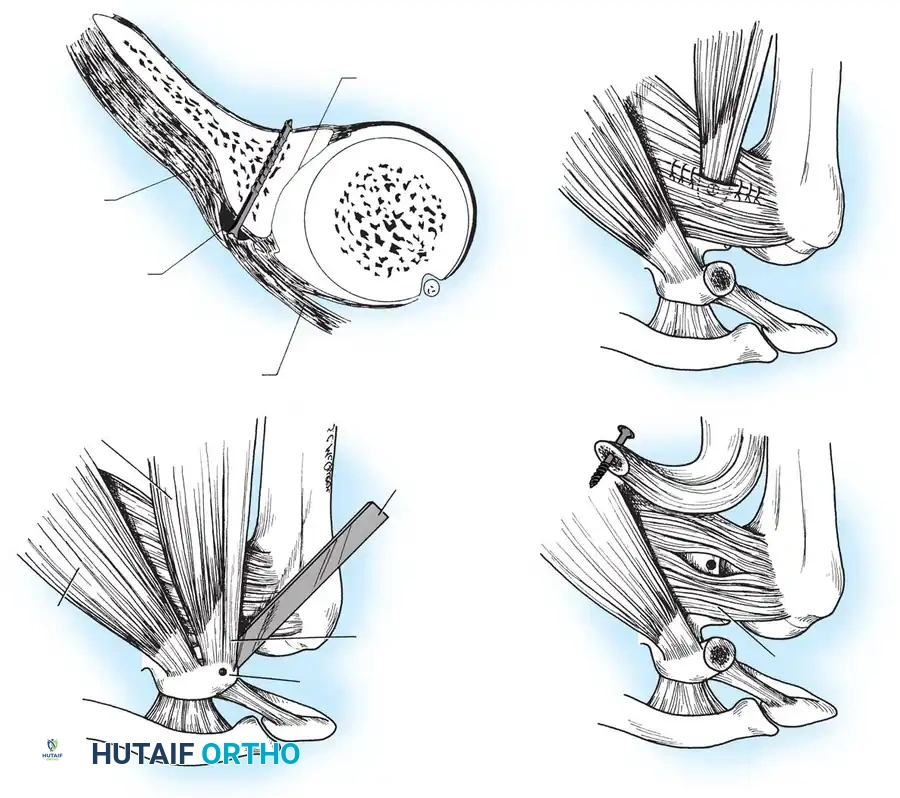

Glenoid Preparation and Labral Repair

The essential step in restoring stability is the anatomical reduction of the capsulolabral complex to a bleeding bone bed on the anterior glenoid rim.

- Debridement: The anterior glenoid neck is decorticated using a motorized burr, rasp, or osteotome to create a bleeding cancellous bed. This promotes robust biological healing of the repaired labrum.

- Mobilization: The scarred, medially displaced labrum (ALPSA lesion) must be fully mobilized using a periosteal elevator until the subscapularis muscle belly is visible anteriorly. The tissue must float freely to be shifted superiorly and laterally.

- Anchor Placement: Suture anchors (typically 3 to 4) are placed along the articular margin of the anteroinferior glenoid (from the 5:30 to 3:00 positions for a right shoulder). Anchors must be inserted at a 45-degree angle to the articular surface to maximize pullout strength and avoid joint penetration.